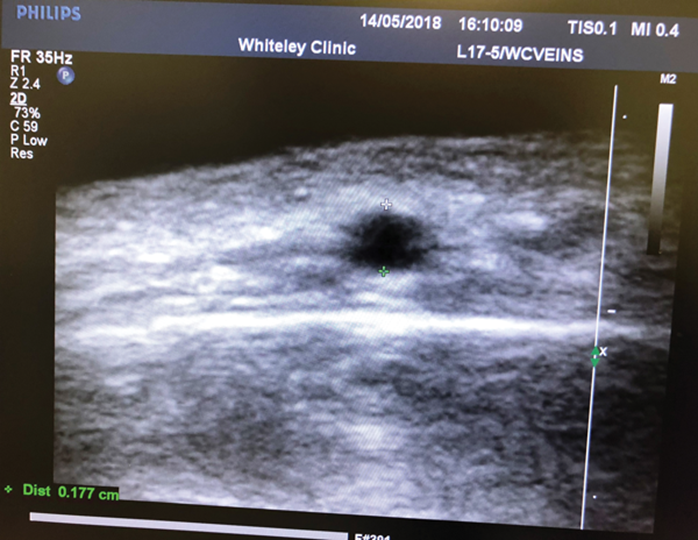

We prefer phlebectomy using local anaesthetic (lignocaine) with adrenaline (epinephrine) to reduce bruising. Incisions are made using the smallest possible blade and in line with where skin creases will develop if there are none present. Of course if there are skin creases already, incisions should be made within these. Phlebectomy hooks can be used but it should be noted that these veins are very small and difficult to remove. They are often adhered to the skin and access with the hook is difficult due to the muscles of facial expression (frontalis muscle on forehead) inserting into the skin around the vein. With experience, good results can be obtained (Figure 6) but we have found it is a long learning curve to get good at this and so we restrict the practice to one surgeon in our clinic. In addition, we have ready access to vascular ultrasound which is helpful in identifying the position of veins, checking there is no arterial flow and ensuring that there is no abnormality associated with the target vein (Figure 7).

Figure 7: Ultrasound of forehead vein in transverse section. The scale shows that the vein is 0.177 cm in diameter and is about the same depth.